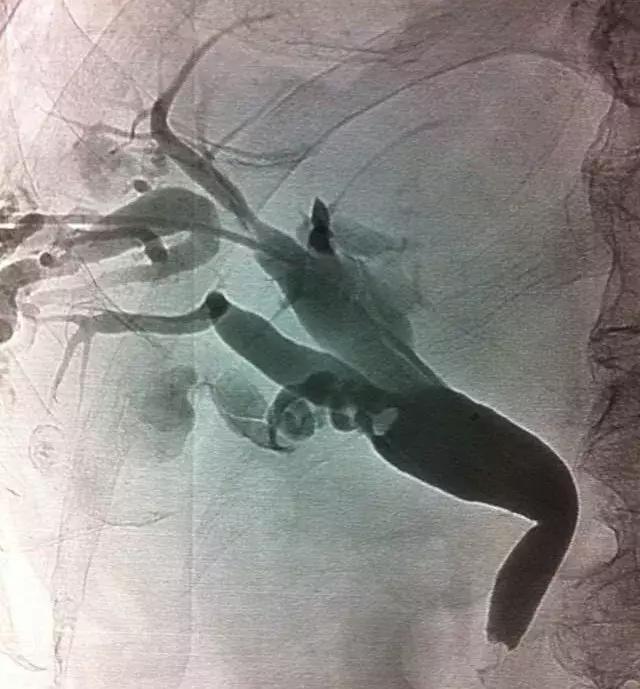

ERCP治疗

对于轻度或中度急性胆管炎伴胆管结石且无抗凝治疗或凝血功能异常的病人,可考虑在胆管引流的同时进行内镜下括约肌切开术(EST)清除结石,但EST常见的并发症有胰腺炎、十二指肠或胆管穿孔、出血和感染等,同时切开括约肌可能造成肠液返流,将来再次诱发胆管炎,因此有些医生选择气囊扩张壶腹部再行取石,这样能保留括约肌的功能。

对取石困难的病人,如结石较大或多发结石等,可以分两次进行:先行ENBD胆管引流,待炎症得到控制后再经内镜清除结石。

若因ERCP技术问题不能建立胆道引流,可通过经皮肝穿刺胆道引流(PTCD),如果胆管扩张不明显,另一个替代方法是经皮经肝胆囊穿刺引流(PTGD)。

PTCD治疗